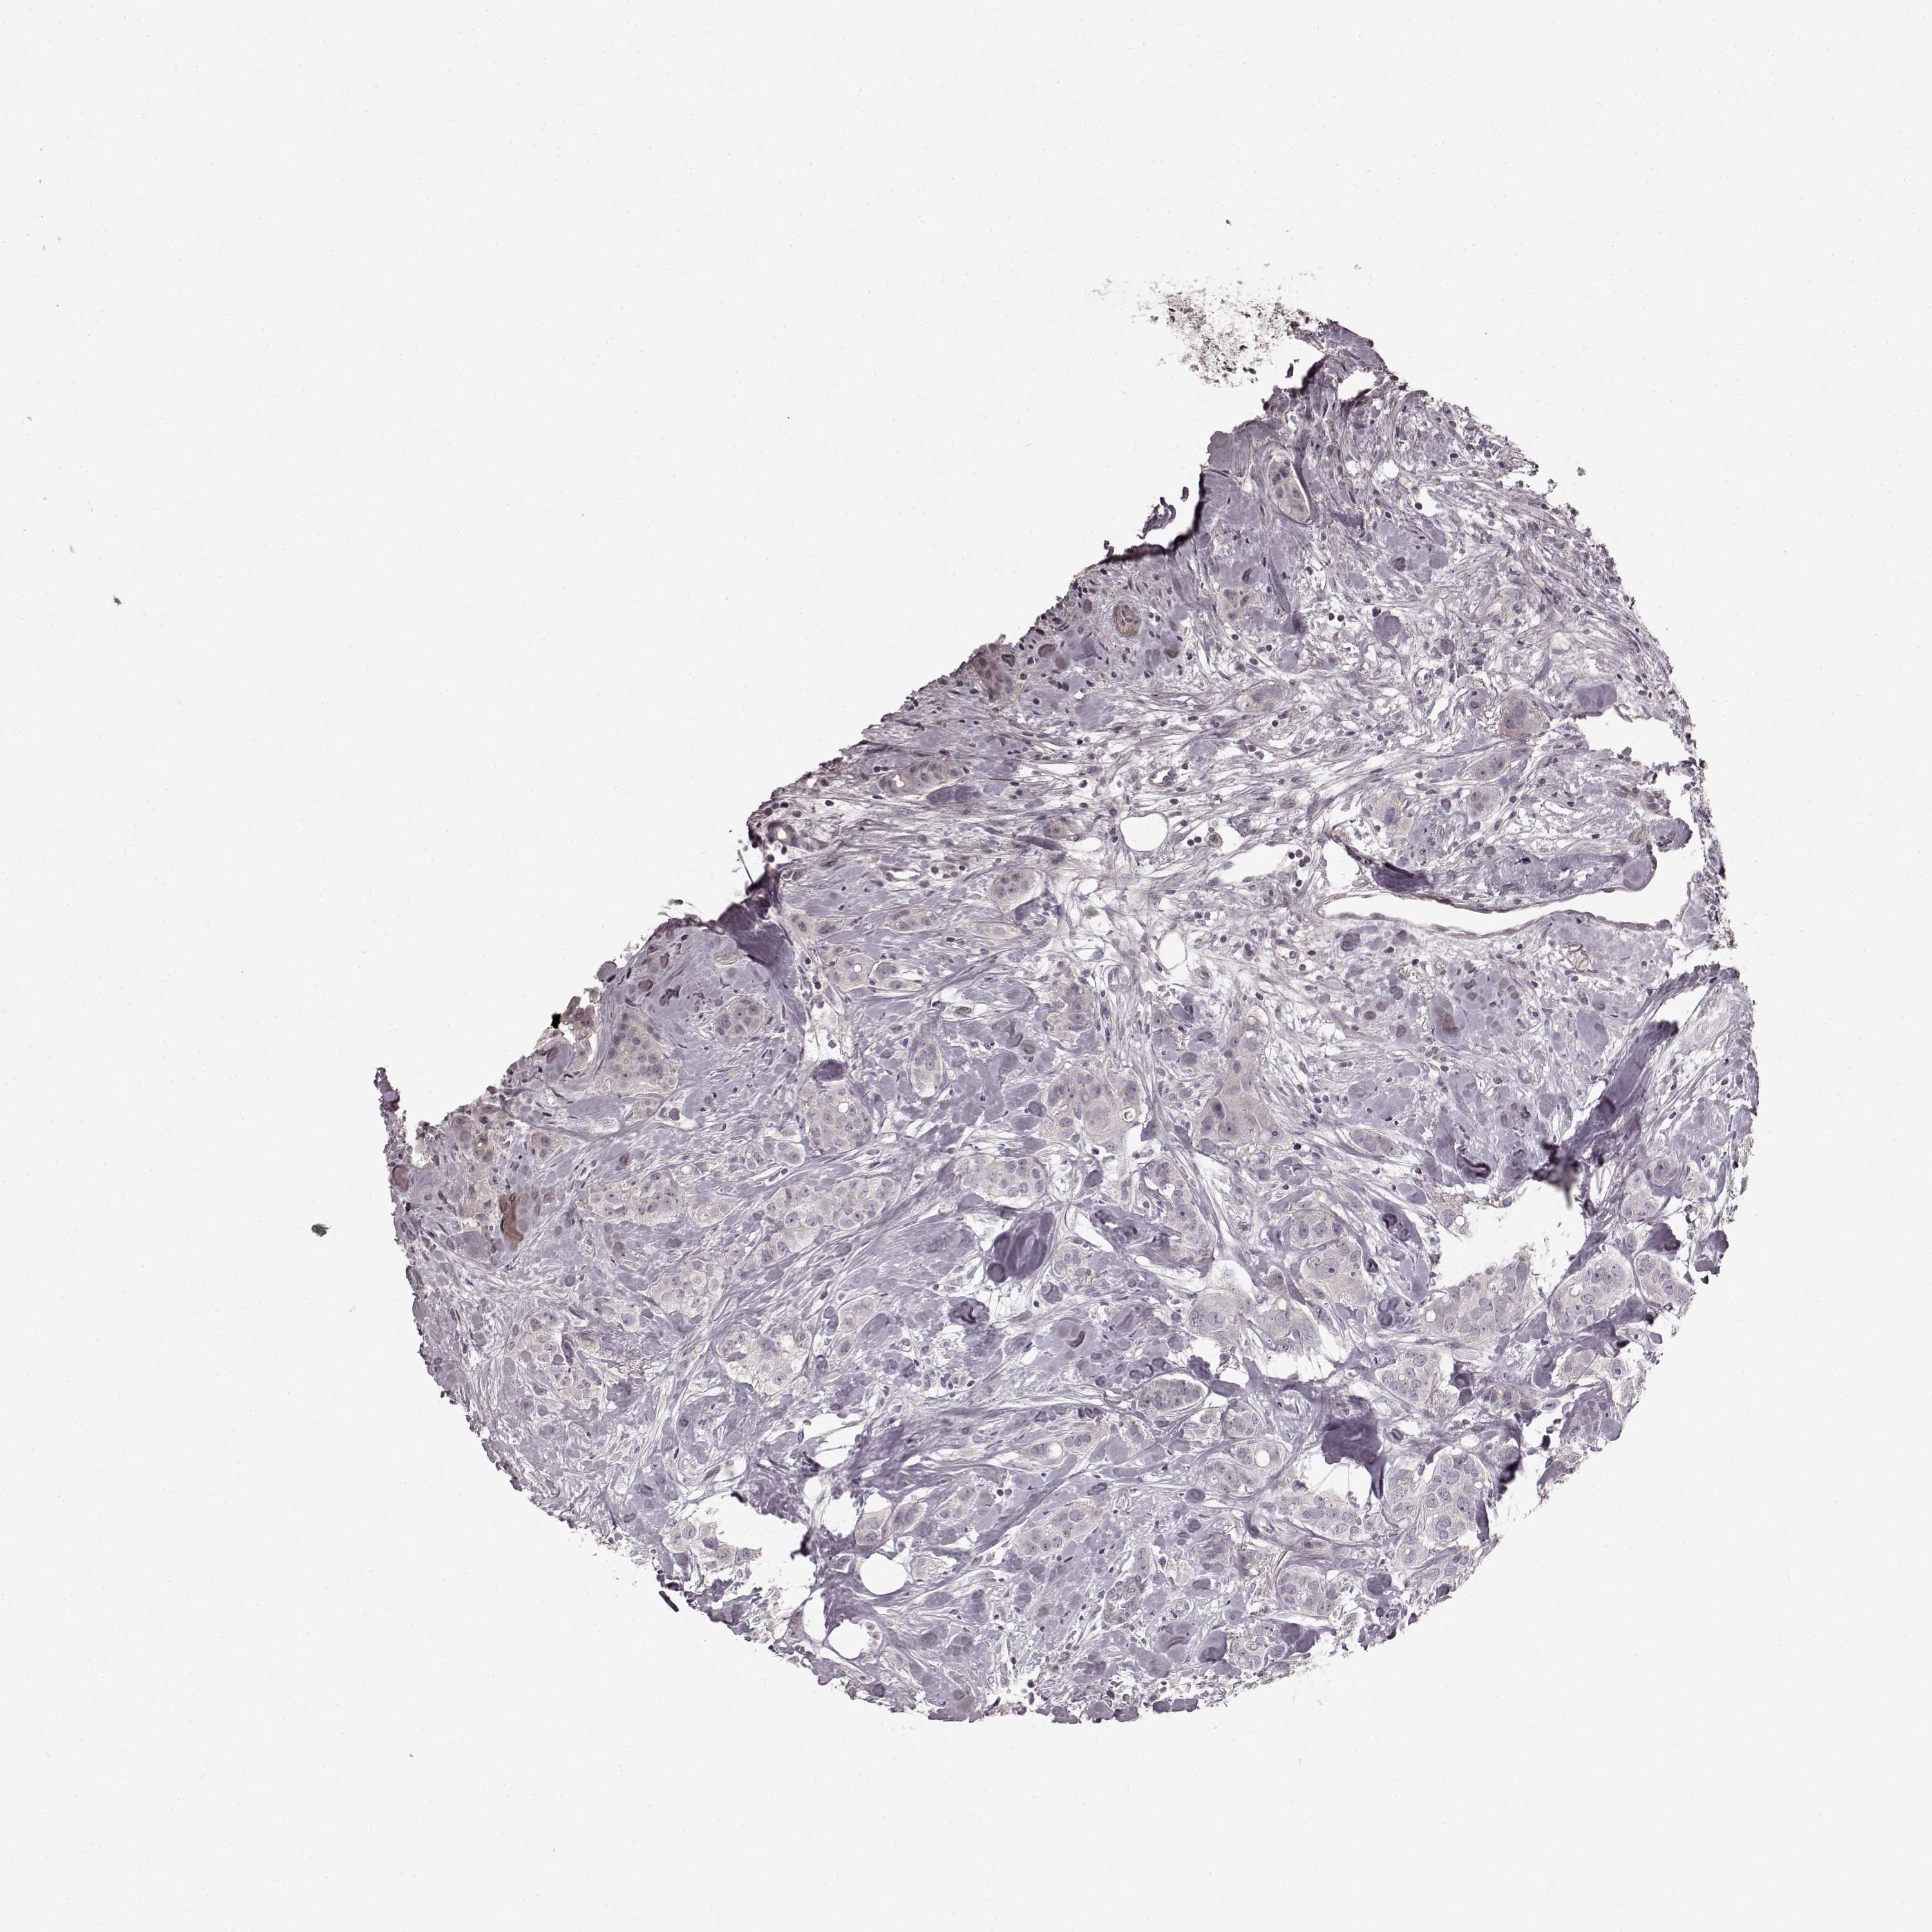

CANCER BREAST CANCER Show tissue menu

BRCA TCGA BRCA VALIDATION PROTEIN EXPRESSION